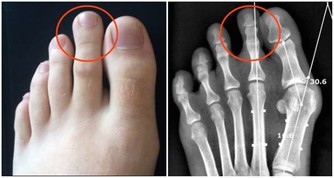

狼瘡和類風濕性關節炎有兩個可怕的共同點:更可能影響女性,都會增加心髒病的風險。這一切都歸結於炎症,炎症損害血管,導致斑塊積聚。